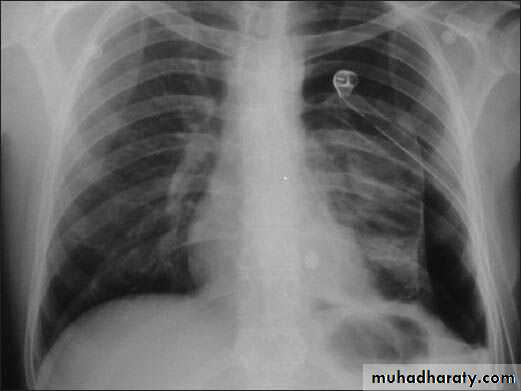

Patient with fever, rigor and dyspnea